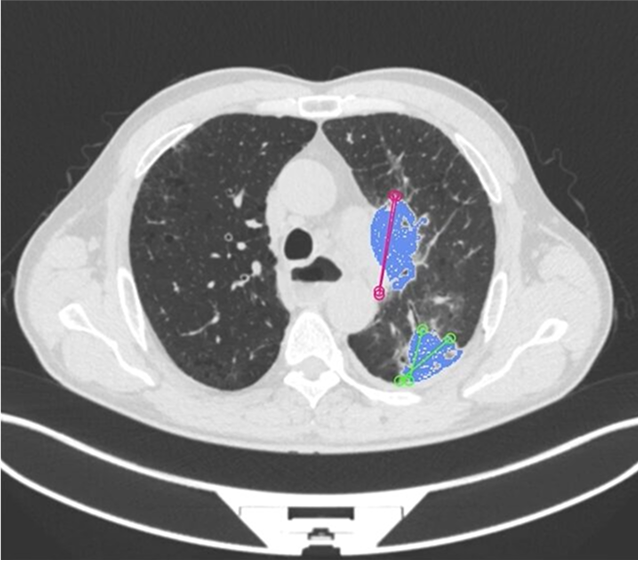

AI models trained with well-annotated data can detect patterns that may be missed by the human eye. For example, annotated radiology images can help AI systems detect tumors or microfractures at an early stage.

AI can detect anomalies like lung infections, bone fractures, or neurological disorders faster and with high accuracy.

AI models trained with annotated images help identify tumors, classify their stages, and track growth over time.